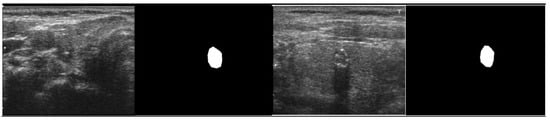

The ground truth (GT) mask associated with each thyroid ultrasound picture is required to differentiate the nodule part for the training procedure. The labelme [23] annotates the thyroid images before creating a polygon mask for each image. Figure 3 shows an example of the original image and its GT counterpart. The interpretations of ultrasound images by labelme software are saved as JSON files, comprised of polygon points for the nodule region attributed to 0 or 1. The pixels inside the enclosing polygon associated with the nodule region have a value of 1, while the remainder are considered background having a value of 0.

This research aims to create a deep learning framework that can recognize thyroid nodules in ultrasound images effectively. Despite the considerable variances in the ultrasound data, the proposed model outperformed U-Net quantitatively and produced highly accurate detection results. The testing results revealed that the proposed model achieved an overall accuracy of 99%, dice score of 97.5%, sensitivity of 98%, IoU of 97.1%, and precision of 97%. In comparison, the benchmark U-Net approach obtained an accuracy of 96%, a precision of 96%, sensitivity of 95.2%, dice score of 95.4%, and IoU of 95.3%. Table 4 shows the comparison of both methods and their respective parameters. The experimental findings show that the proposed method is very accurate, efficient, and reliable. Figure 4 shows the qualitative segmentation results of the proposed method and the benchmark method (U-Net), demonstrating that the proposed method can segment thyroid nodules following the reference standard. In contrast, the state-of-the-art benchmark method (U-Net) cannot detect in some cases.

Figure 3. Original image and its corresponding GT masks.

Figure 4. Segmentation output results of the proposed and benchmark methods.